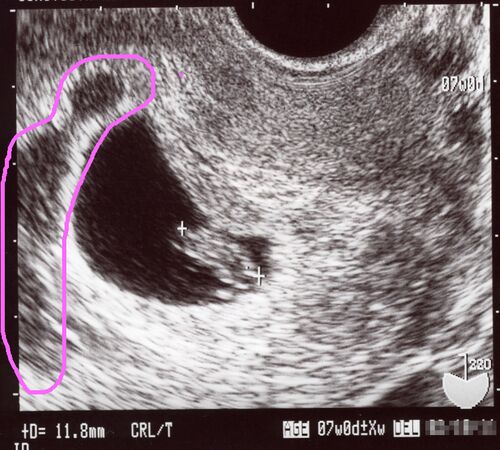

残業中に大出血…絨毛膜下血腫のこと(第一子妊娠時)

第二子妊娠中の現在は15週の終わりで子宮頚管が短くなり、17週の終わりから自宅安静に入っていますが、第一子妊娠時は、なんと6週の時から自宅安静でした。(その後36週で正期産に入るまで…!半年以上家に引きこもってた計算になりますね…!) 原因は…絨毛膜…